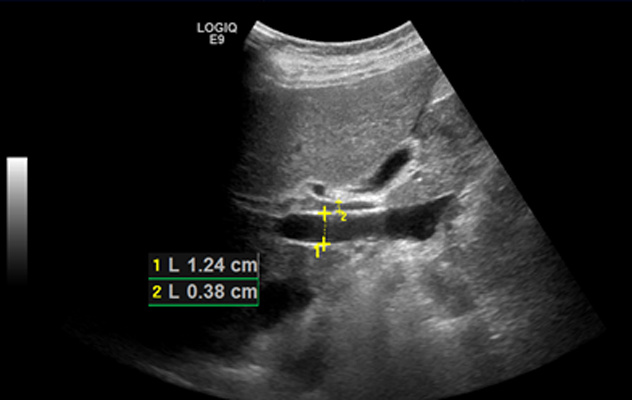

При ультразвуковом исследовании: печень увеличена, правая доля КВР: 170 мм

левая доля ВР, толщина: 70 мм. Контуры четкие, умеренно неровные, структура умеренно неоднородная. Воротная вена 16 мм – расширена. При исследовании, выполненном этой пациентке в 2016 году ширина воротной вены была 12 мм – по верхней границе нормы.